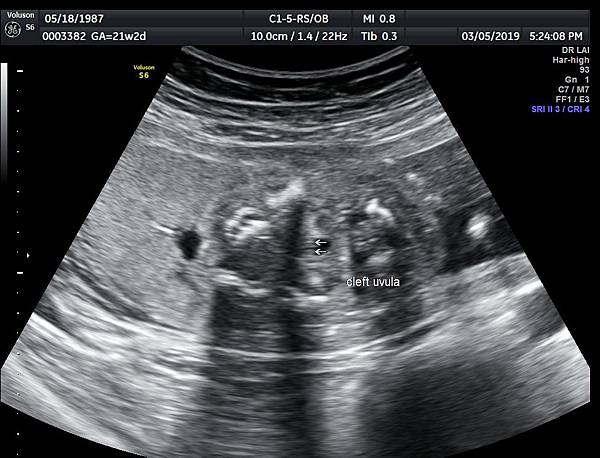

一個檢查如果要花很長的時間才能完成,這樣的檢查無法變成常規的篩檢方式,我已經在我的診所執行懸雍垂檢查一段時間,我檢查懸雍垂大約30 秒,前提是胎兒的臉最佳位置是側躺,其次是側躺偏向上,我的檢查步驟是上顎(含日後大門牙長出的位置)、舌頭、懸雍垂(= equal sign)(附圖1~8),如果超過60秒無法完成,只有兩個原因,一個是胎兒姿勢不適合或喉嚨羊水空間太小,這時候不要硬碰硬,只要先檢查其他部位,等待時機再回來即可,我的經驗是90%的cases都能順利完成這項檢查(肚皮厚的case真的是很難)。

有興趣的同業可以參考我的部落格備忘錄第119、120、127 及 236 這四篇,裡面有我做懸雍垂(uvula)的相關影像。